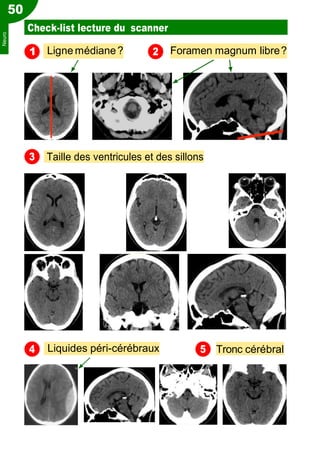

Check-list lecture du scanner

1 Ligne médiane? Foramen magnum libre?

Taille des ventricules et des sillons

Liquides péri-cérébraux Tronc cérébral

3

4

Neuro

Cervelet

Nx gris centraux Subst. blanche Cortex

Lobe Frontal

Lobe Pariétal

Lobe Temporal

Lobe Occipital

Référence : Dr Charles Laurent